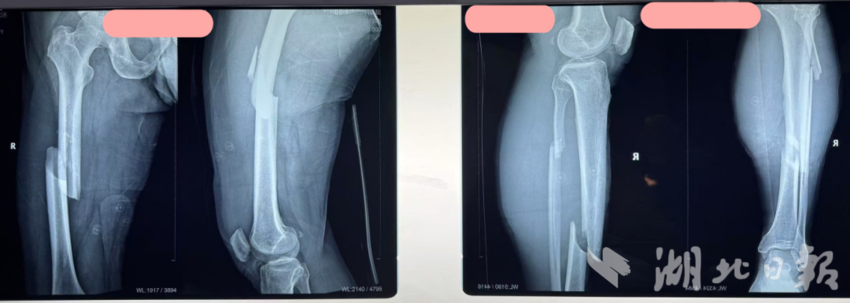

经DR与CT全面排查,初步诊断的“开放性胫骨骨折”仅为表层伤情,患者实际伤情更为危重:右下肢开放性胫骨骨折、股骨干骨折,双侧多发肋骨骨折(左侧8根)伴创伤性气胸,第5腰椎及多处横突骨折,且合并多年高血压病史,身体耐受度差,需立即启动紧急救治方案。

救治团队首先全力稳定患者生命体征,排除手术禁忌。随后,手术团队凭借精湛的显微外科技术,为患者实施右胫骨清创、血管神经吻合等一期手术,在显微镜下精准吻合断裂的大隐静脉,为肢体血供恢复筑牢基础。一周后,患者伤情稳定,团队顺利为其完成股骨干骨折二期内固定术。